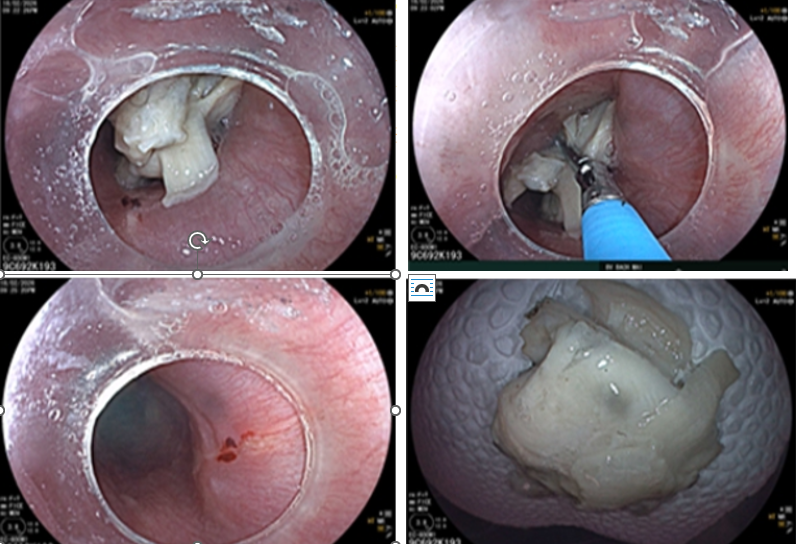

Sau bữa ăn có thịt gà, ông H.V.Q (66 tuổi, Sơn La) thấy nuốt đau, vướng cổ nhưng nghĩ chỉ là “mắc xương nhẹ”. Một ngày sau, tình trạng không giảm, ông được chuyển tới Bạch Mai. Chụp cắt lớp vi tính cho thấy mảnh xương dài gần 3cm mắc ngang thực quản, nghi gây tổn thương thành thực quản.

Nội soi xác định xương gà đã găm vào niêm mạc, tạo vết rách nhỏ.

May mắn, dị vật được lấy ra kịp thời. Tuy nhiên, PGS.TS. Nguyễn Công Long – Giám đốc Trung tâm Tiêu hóa Gan mật cho biết: “Nếu để muộn, xương sắc nhọn có thể gây thủng thực quản, nhiễm trùng trung thất – biến chứng rất nặng và khó điều trị.”